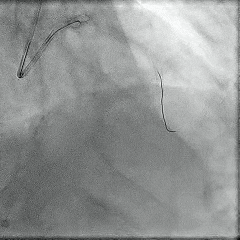

冠脉造影提示:右优势型,左主干未见明显狭窄;前降支中远段可见最重约80%×25mm狭窄,最重处位于第三对角支发出后,回旋支未见明显狭窄;右冠远段内膜光滑。

冠脉造影:

冠脉功能学全面评估:

▶LAD IMR:58(+);FFR:0.82。